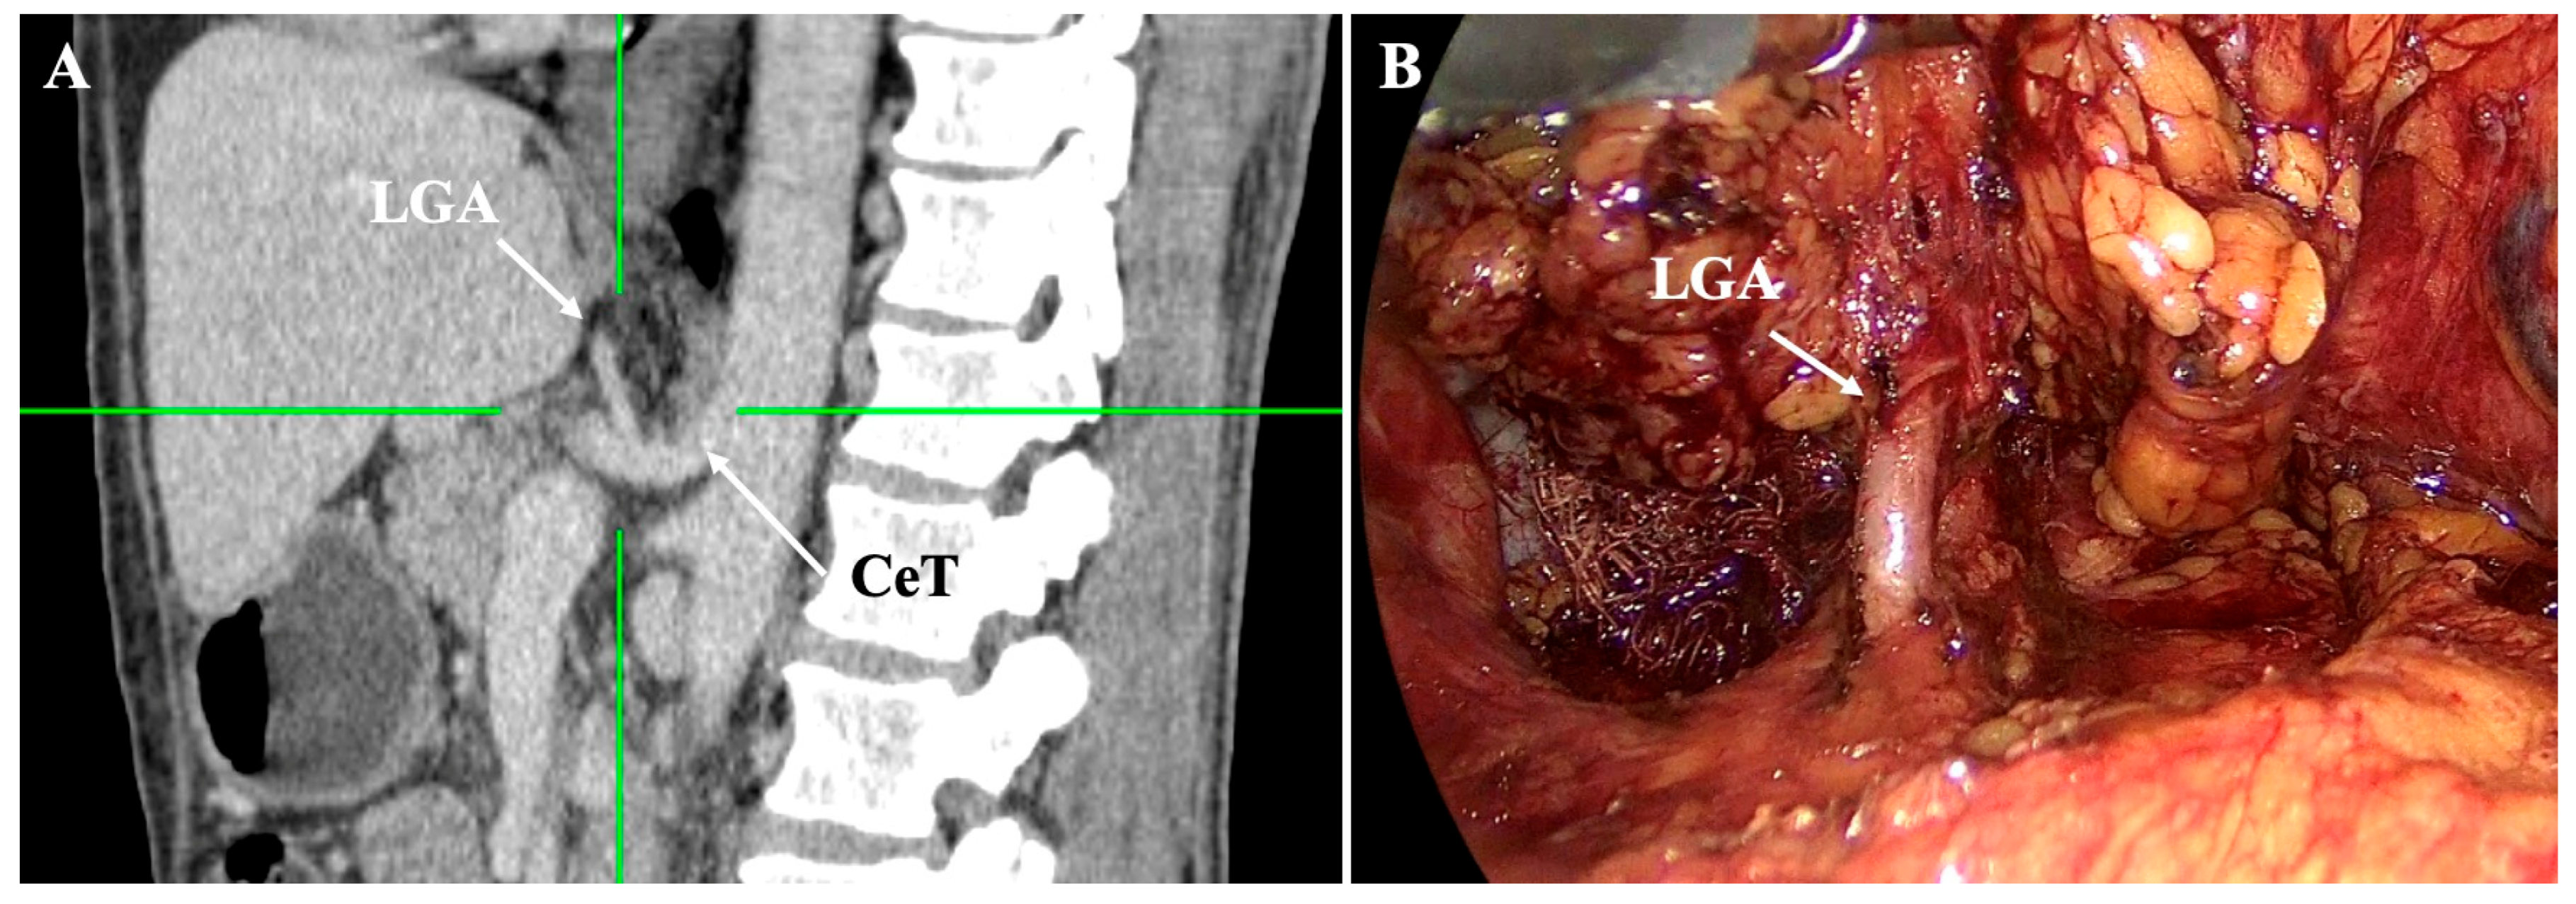

- Lesser curvature and suprapancreatic corridor (stations 7, 8a, 9, 11p): the LGV most often courses posterior to the CHA or anterior to the LGA; recognizing this pattern helps avoid avulsion during high ligation of the LGA and station-7 dissection [30]. Classify the LGV preoperatively relative to the CHA/SA/pancreas. Intraoperative video-based classification in 217 laparoscopic radical gastrectomy cases found type I (LGV running between the CHA posteriorly and the CA-Figure 4) to be most common (56%), whereas type IV (between SA posteriorly and CA-Figure 5) carried the highest bleeding risk (42%) and was an independent predictor of LGV injury on multivariable analysis [32,45] (Figure 4 and Figure 5). 3D MDCT classifications also emphasize that the LGV may terminate variably into the PV, SV, or their confluence—information that guides safe exposure at the pancreatic head and coeliac axis [40]. When a replaced/accessory left hepatic artery arises from the LGA, D2 dissection must preserve arterial inflow while clearing nodal tissue—an approach illustrated in operative atlases focused on variation-aware D2 technique [6].